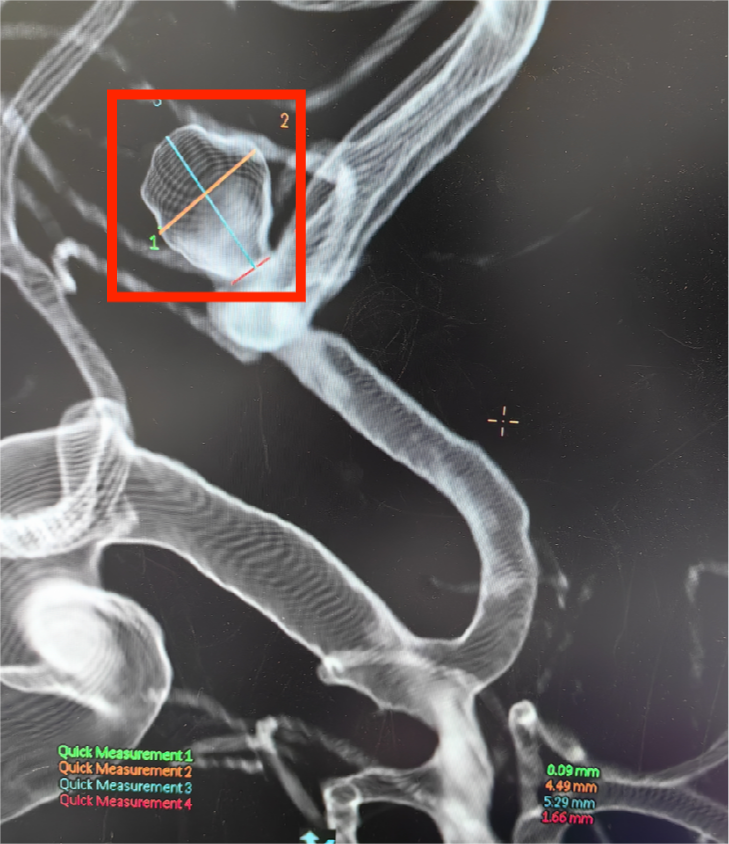

着急的家人立刻拨打 120,王先生很快被送往南京江北医院急诊。到院后急诊立刻进行紧急救治并进行检查,头颅 CT 显示他蛛网膜下腔出血,随后进行头颅 CTA 检查,结果显示王先生前交通动脉瘤,考虑前交通动脉瘤破裂,被神经外科收治住院。

鉴于动脉瘤的大小、位置及王先生的整体健康状况,神经外科团队制定了经导管颅内动脉瘤弹簧圈栓塞术,在与王先生家属进行了深入的沟通,详细解释了手术的必要性和可能的风险,并得到了他们的充分理解和同意。

吕忠中主任介绍,脑动脉瘤具有发病急、死亡致残率高等特点,传统开颅手术创伤大,风险高,并发症及后遗症重,介入栓塞是现在动脉瘤治疗的首选术式。通过股动脉穿刺,在动脉血管内向动脉瘤放置微导管,再通过微导管向动脉瘤内填塞弹簧圈,致密填塞后,从而达到治愈动脉瘤防止出血的目的。